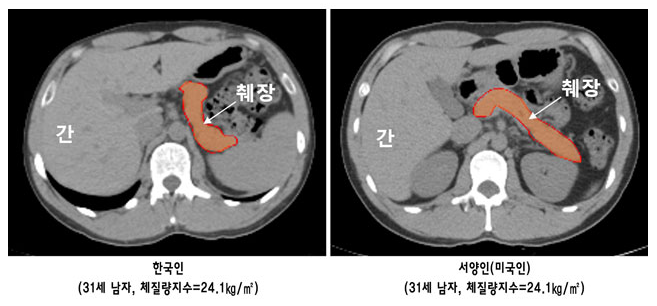

한국의 전통적인 식단은 고당분, 고탄수화물을 기반으로 합니다. 주식인 백미는 포도당의 주요 원천이며, 이외에도 짜장면, 국수와 같은 면류는 한국인의 췌장에 큰 부담을 주는 식품입니다. 이러한 식습관은 당뇨병으로 가는 지름길이 될 수 있으며, 국민 건강을 위협하는 중요한 요소로 작용합니다.

근육을 키우기 위한 벌크업 방식의 식단이 인기를 끌고 있지만, 이 역시 한국인의 췌장 기능에 부담을 줍니다. 탄수화물과 단백질을 많이 섭취하는 이러한 식단은 서양인에게는 적합할 수 있으나, 한국인에게는 인슐린 저항성을 증가시켜 당뇨병 발생 위험을 높일 수 있습니다.